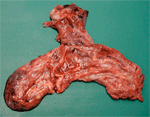

Thoracoscopic resection was done after 6 weeks and the gross anatomic appearance showed a distinct air-filled entity, separate from left upper and left lower lobes. There was small tissue-band attachment to left lower lobe with vascular adhesions to pleura.

![]() Figure 11 |